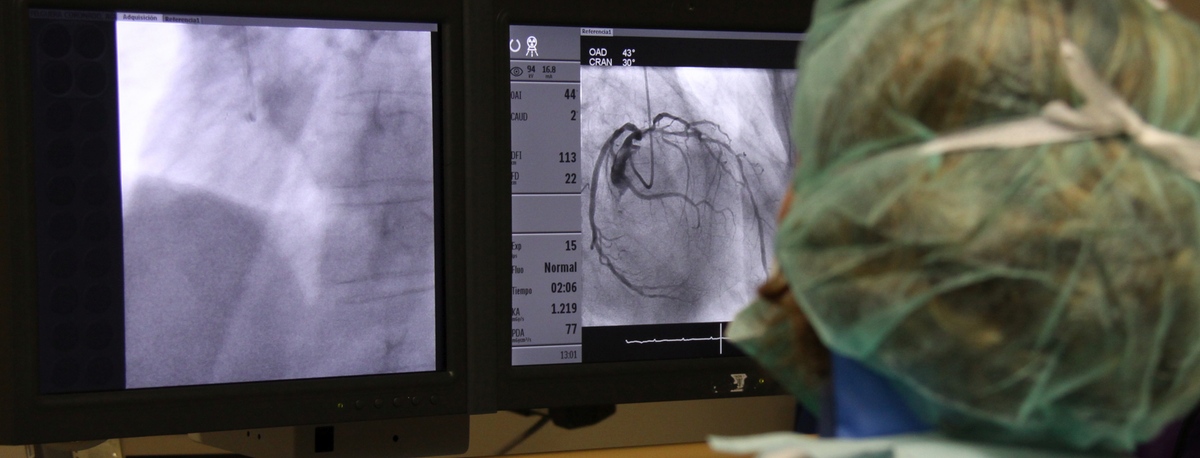

Instituto del Corazón Quirónsalud Teknon

Tractaments i especialitats

A l'institut comptem amb especialistes en angiologia, cirurgia vascular i endovascular per al diagnòstic i seguiment de les malalties de l'aparell circulatori. L'embòlia cerebral i el tromboembolisme pulmonar són algunes de les causes principals de mort deguda a un problema vascular.

El nostre equip és especialista en tècniques mínimament invasives, utilitzant tècniques endovasculars, sense cirurgia, que permeten implantar pròtesis vasculars per resoldre dilatacions o aneurismes de les artèries. També oferim tots els tractaments de la patologia venosa i arterial perifèrica, incloent-hi les malalties de les artèries caròtides.